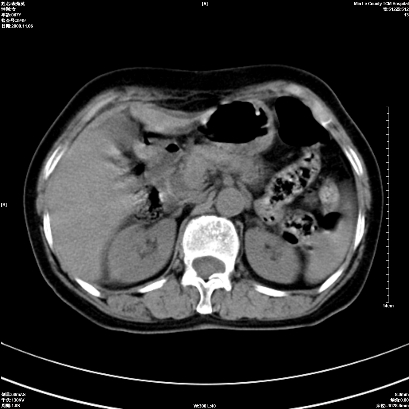

以下是引用卜一在2008-11-6 15:58:00的发言:[br]胰头略增大,胆总管扩张,末端渐行性狭窄。多考虑:胰头癌!建议增强!